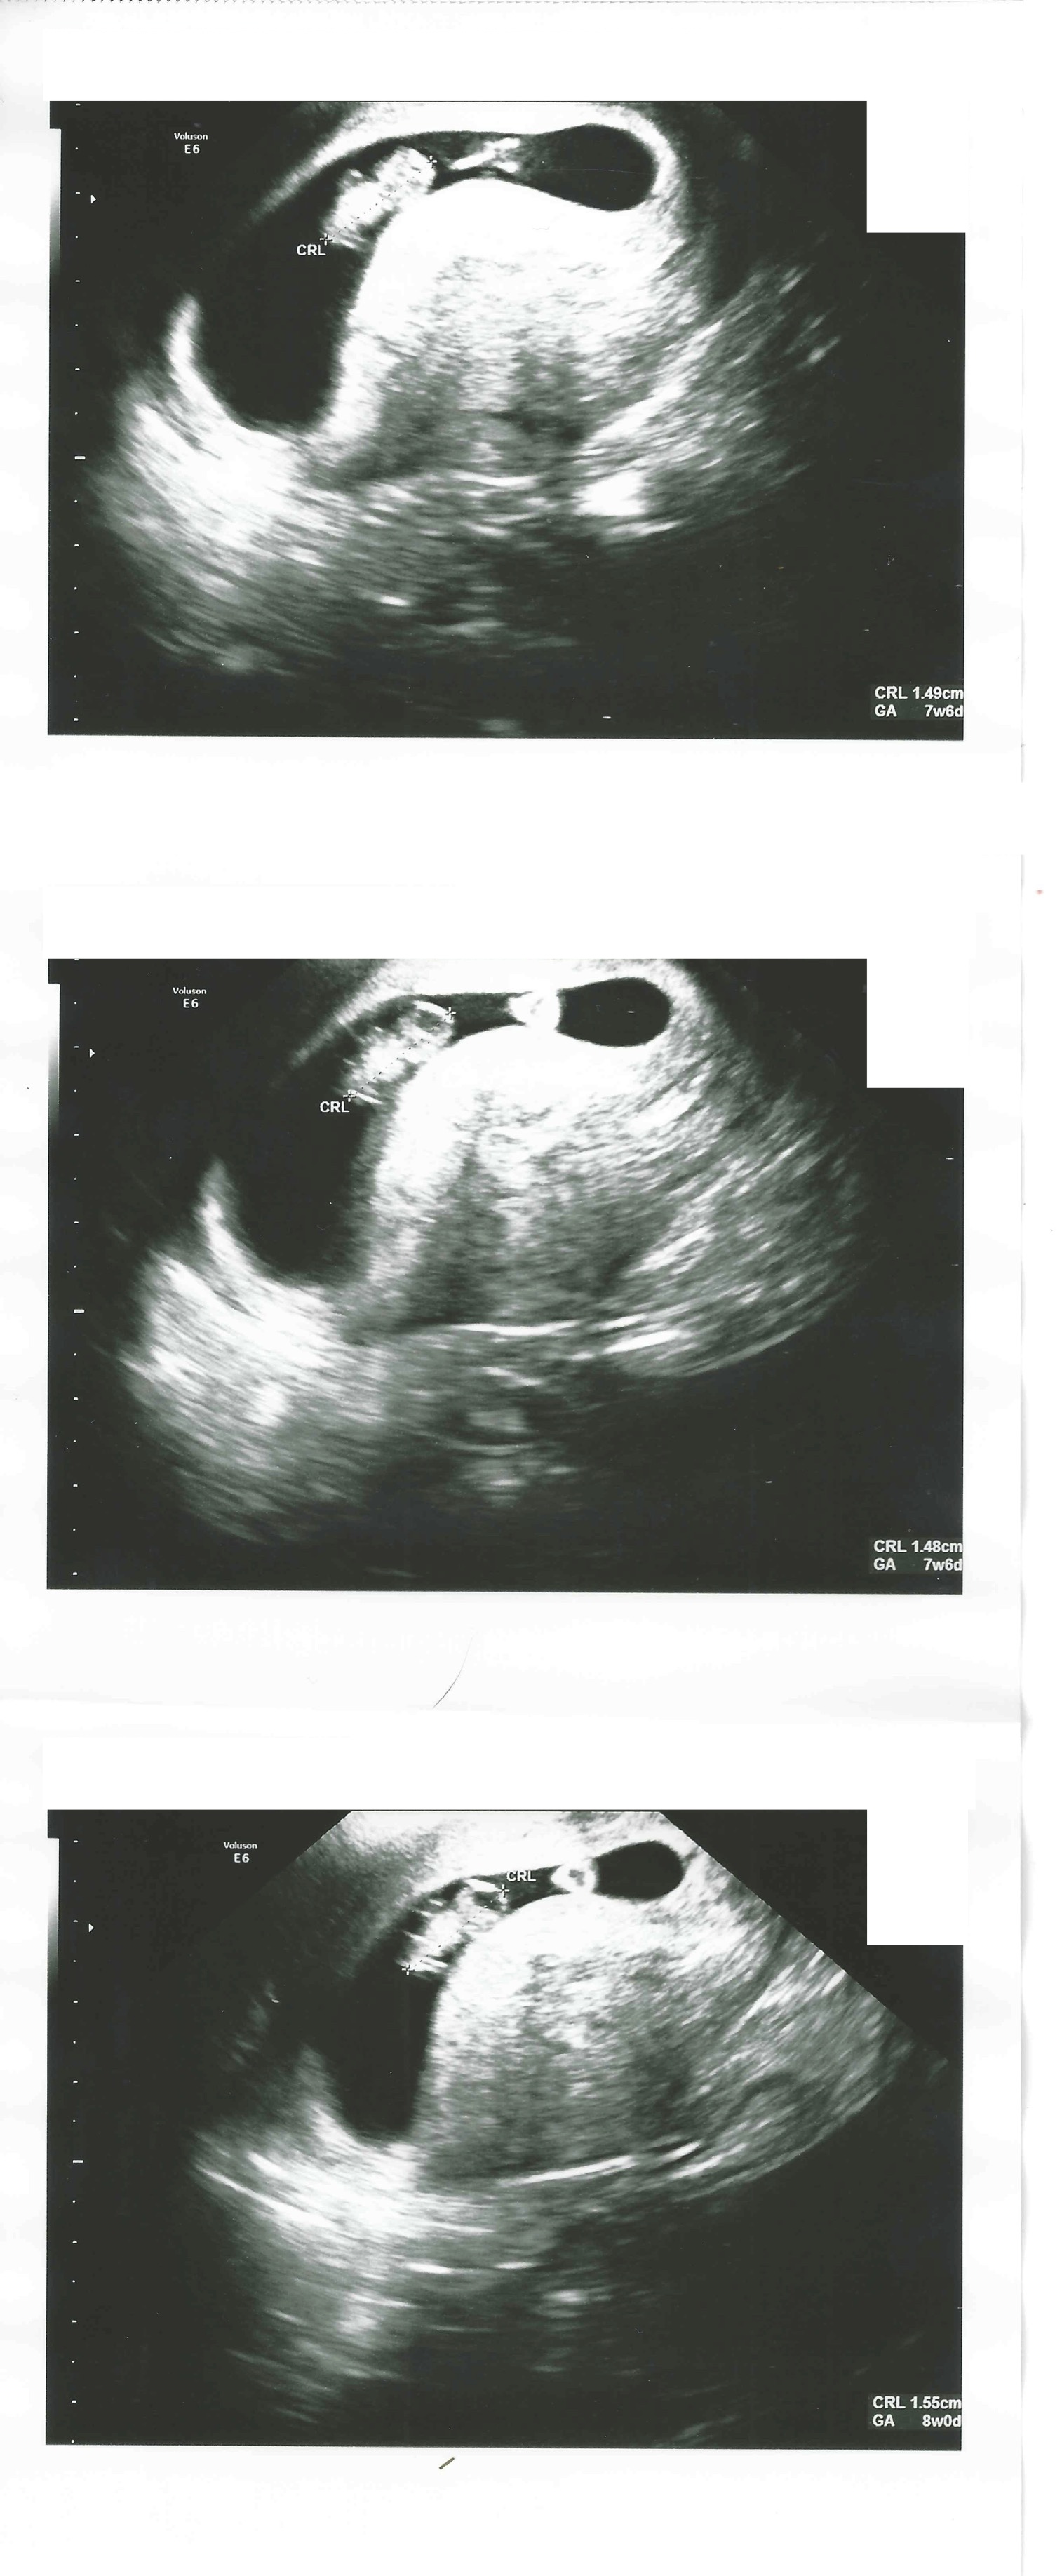

8 weken